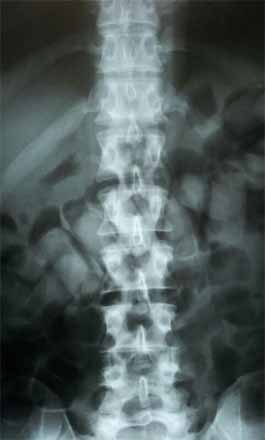

“Os policiais suspeitaram dos poloneses e, após uma viatura minuciosa, foram localizadas 36 cápsulas de cocaína nas partes íntimas dos homens. Todos foram levados para o PS de Assis onde o exame de raio-X constatou que todos tem drogas no estômago”, explica o capitão da Polícia Rodoviária, Adriano Aranão.

O exame de raio-X constatou que todos estavam drogas no estômago